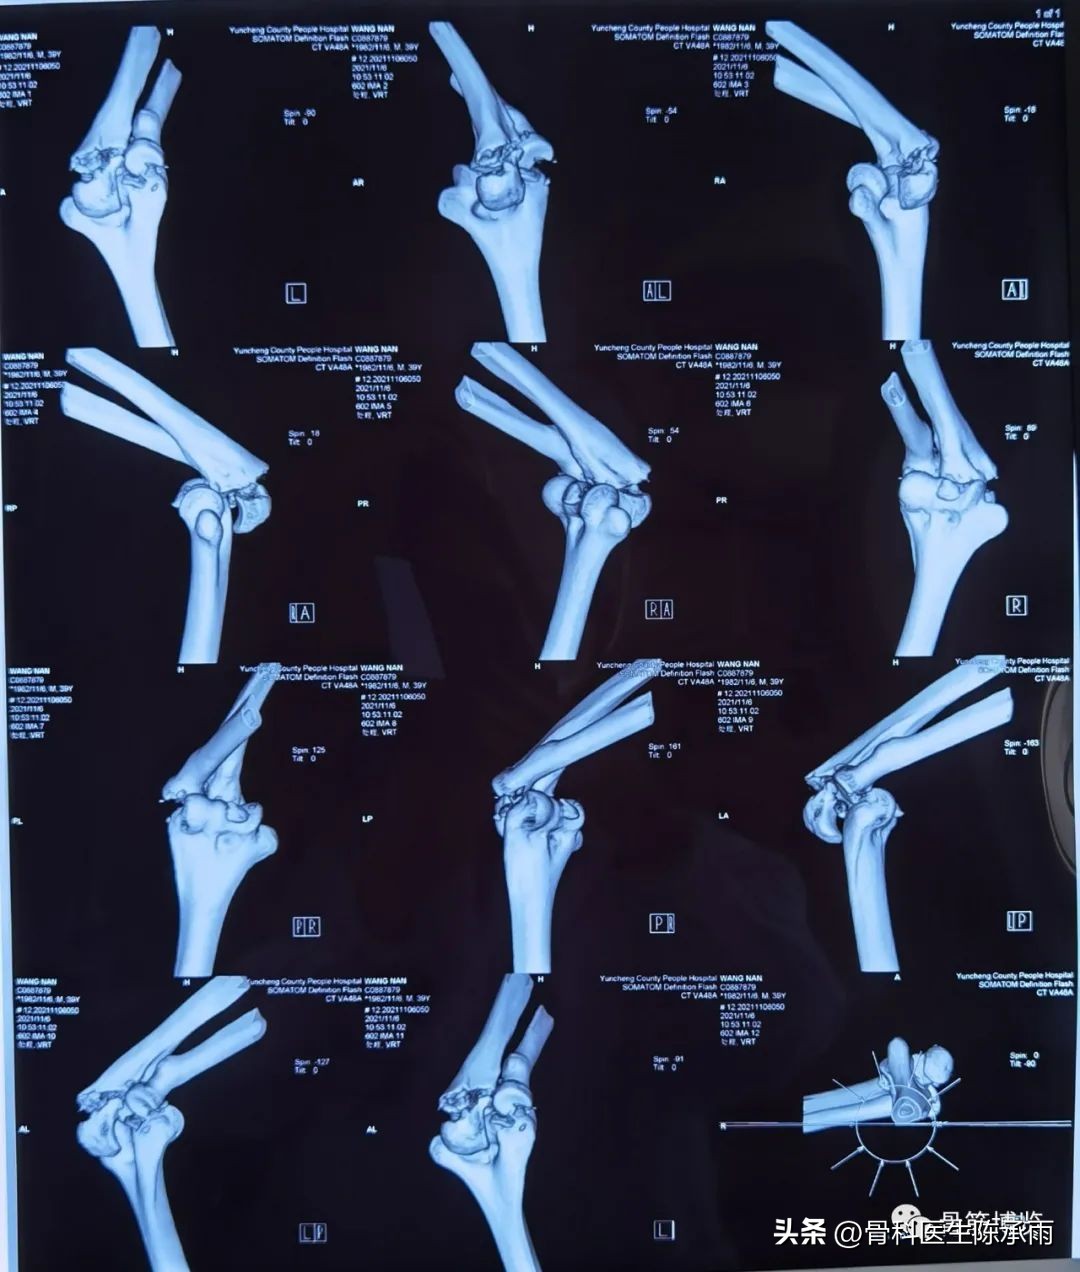

这是最近的1例手术,合并了尺骨鹰嘴骨折,采用后侧入路

术前影像